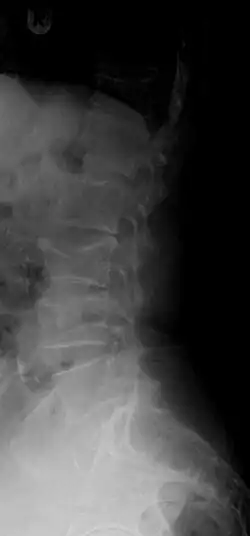

A compression fracture is a collapse of a vertebra. It may be due to trauma or due to a weakening of the vertebra (compare with burst fracture). This weakening is seen in patients with osteoporosis or osteogenesis imperfecta, lytic lesions from metastatic or primary tumors,[1] or infection.[2] In healthy patients, it is most often seen in individuals suffering extreme vertical shocks, such as ejecting from an ejection seat. Seen in lateral views in plain x-ray films, compression fractures of the spine characteristically appear as wedge deformities, with greater loss of height anteriorly than posteriorly and intact pedicles in the anteroposterior view.[3]

Compression fractures are usually diagnosed on spinal radiographs, where a wedge-shaped vertebra may be visible or there may be loss of height of the vertebra. In addition, bone density measurement may be performed to evaluate for osteoporosis. When a tumor is suspected as the underlying cause, or the fracture was caused by severe trauma, CT or MRI scans may be performed.